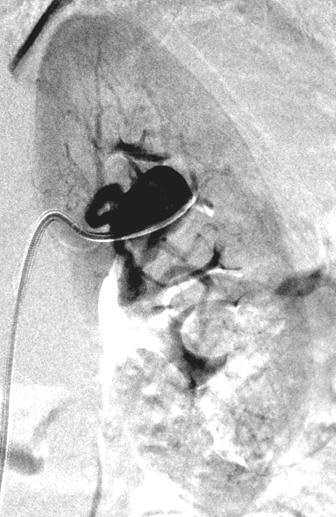

早期弥漫性皮肤系统硬化,手指和面部皮肤增厚。偶然发现肾动脉瘤 治疗技术 技术 - 引导导管在左肾动脉开口 - 将COBRA导管推进到后肾动脉中 - 置换0.35长导丝到远端肾下极动脉 分支痉挛 350mcg 硝酸甘油 右肾下极动脉立即痉挛:硝酸甘油 硝酸甘油部分有效;停

早期弥漫性皮肤系统硬化,手指和面部皮肤增厚。偶然发现肾动脉瘤

治疗技术

技术

- 引导导管在左肾动脉开口

- 将COBRA导管推进到后肾动脉中

- 置换0.35长导丝到远端肾下极动脉

分支痉挛

350mcg 硝酸甘油

右肾下极动脉立即痉挛:硝酸甘油

硝酸甘油部分有效;停止手术?更多的肝素?

5 mm x 22 mm 覆膜支撑架

动脉瘤消失

肾下极血流消失

通过包膜的侧支循环血流

没有内脏动脉瘤逆行充盈

最后一次血管扩张药物后